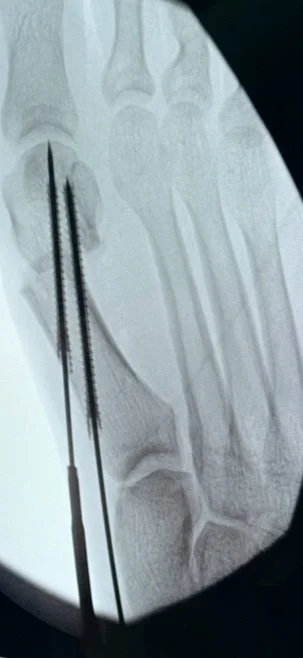

• Module 2: Proximal Interphalangeal Joint Fusion for Treatment of Hammertoe Deformity

• Module 3: Distal Metatarsal and Digital Osteotomies for Treatment of Mild to Moderate HAV